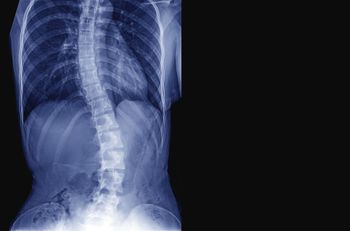

Axial spondyloarthritis (axSpA) is never a straightforward diagnosis. In this slideshow, we highlight 11 disease manifestations associated with axSpA.

Delays in diagnosing axSpA are troubling, write the authors of a report in the journal Rheumatology. Delays of up to 10 years have been reported. Not all physicians may be familiar with the signs and symptoms of axSpA.